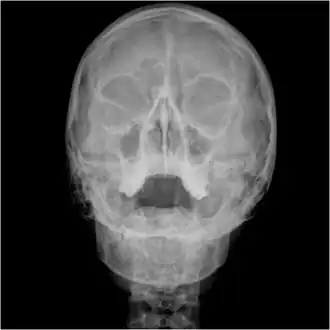

Waters view showing diffuse prominent mucosal thickening in the right maxillary sinus and mild nmucosal thickening in the left maxillary sinus.

Orbital x-ray or orbital radiography is an x-ray of both left and right eye sockets, to include the Frontal Sinuses and Maxillary Sinuses.

An orbital x-ray usually requires only one view unless the requester is looking for evidence of metallic fragments, in which case two projections can be made. One with the eyes looking up, one with the eyes looking down. These views will show any movement of fragments and helps rule out false positives / artefacts which may be present on the image receiver. Two other important views are the Water's view which helps visualise the anterior orbital floor and maxillary sinuses; and the Caldwell view which helps to visualise the frontal and ethmoid sinuses and posterior orbital floor.[3]